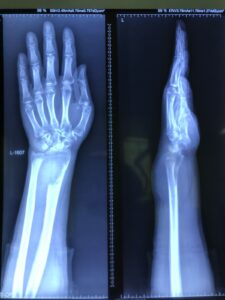

उत्तर: कलाई या घुटने के पास लगातार दर्द, सूजन या बिना चोट के हड्डी टूटना जीसीटी का संकेत हो सकता है। तुरंत ऑर्थो सर्जन से संपर्क करें। डॉक्टर पहले एक्स-रे कराते हैं, जो विशिष्ट लुक देता है (चित्र 2 देखें)। फिर एमआरआई, सीटी स्कैन या एचआरसीटी जैसे टेस्ट होते हैं। सर्जरी मुख्य इलाज है, जिसमें ट्यूमर हटाया जाता है।